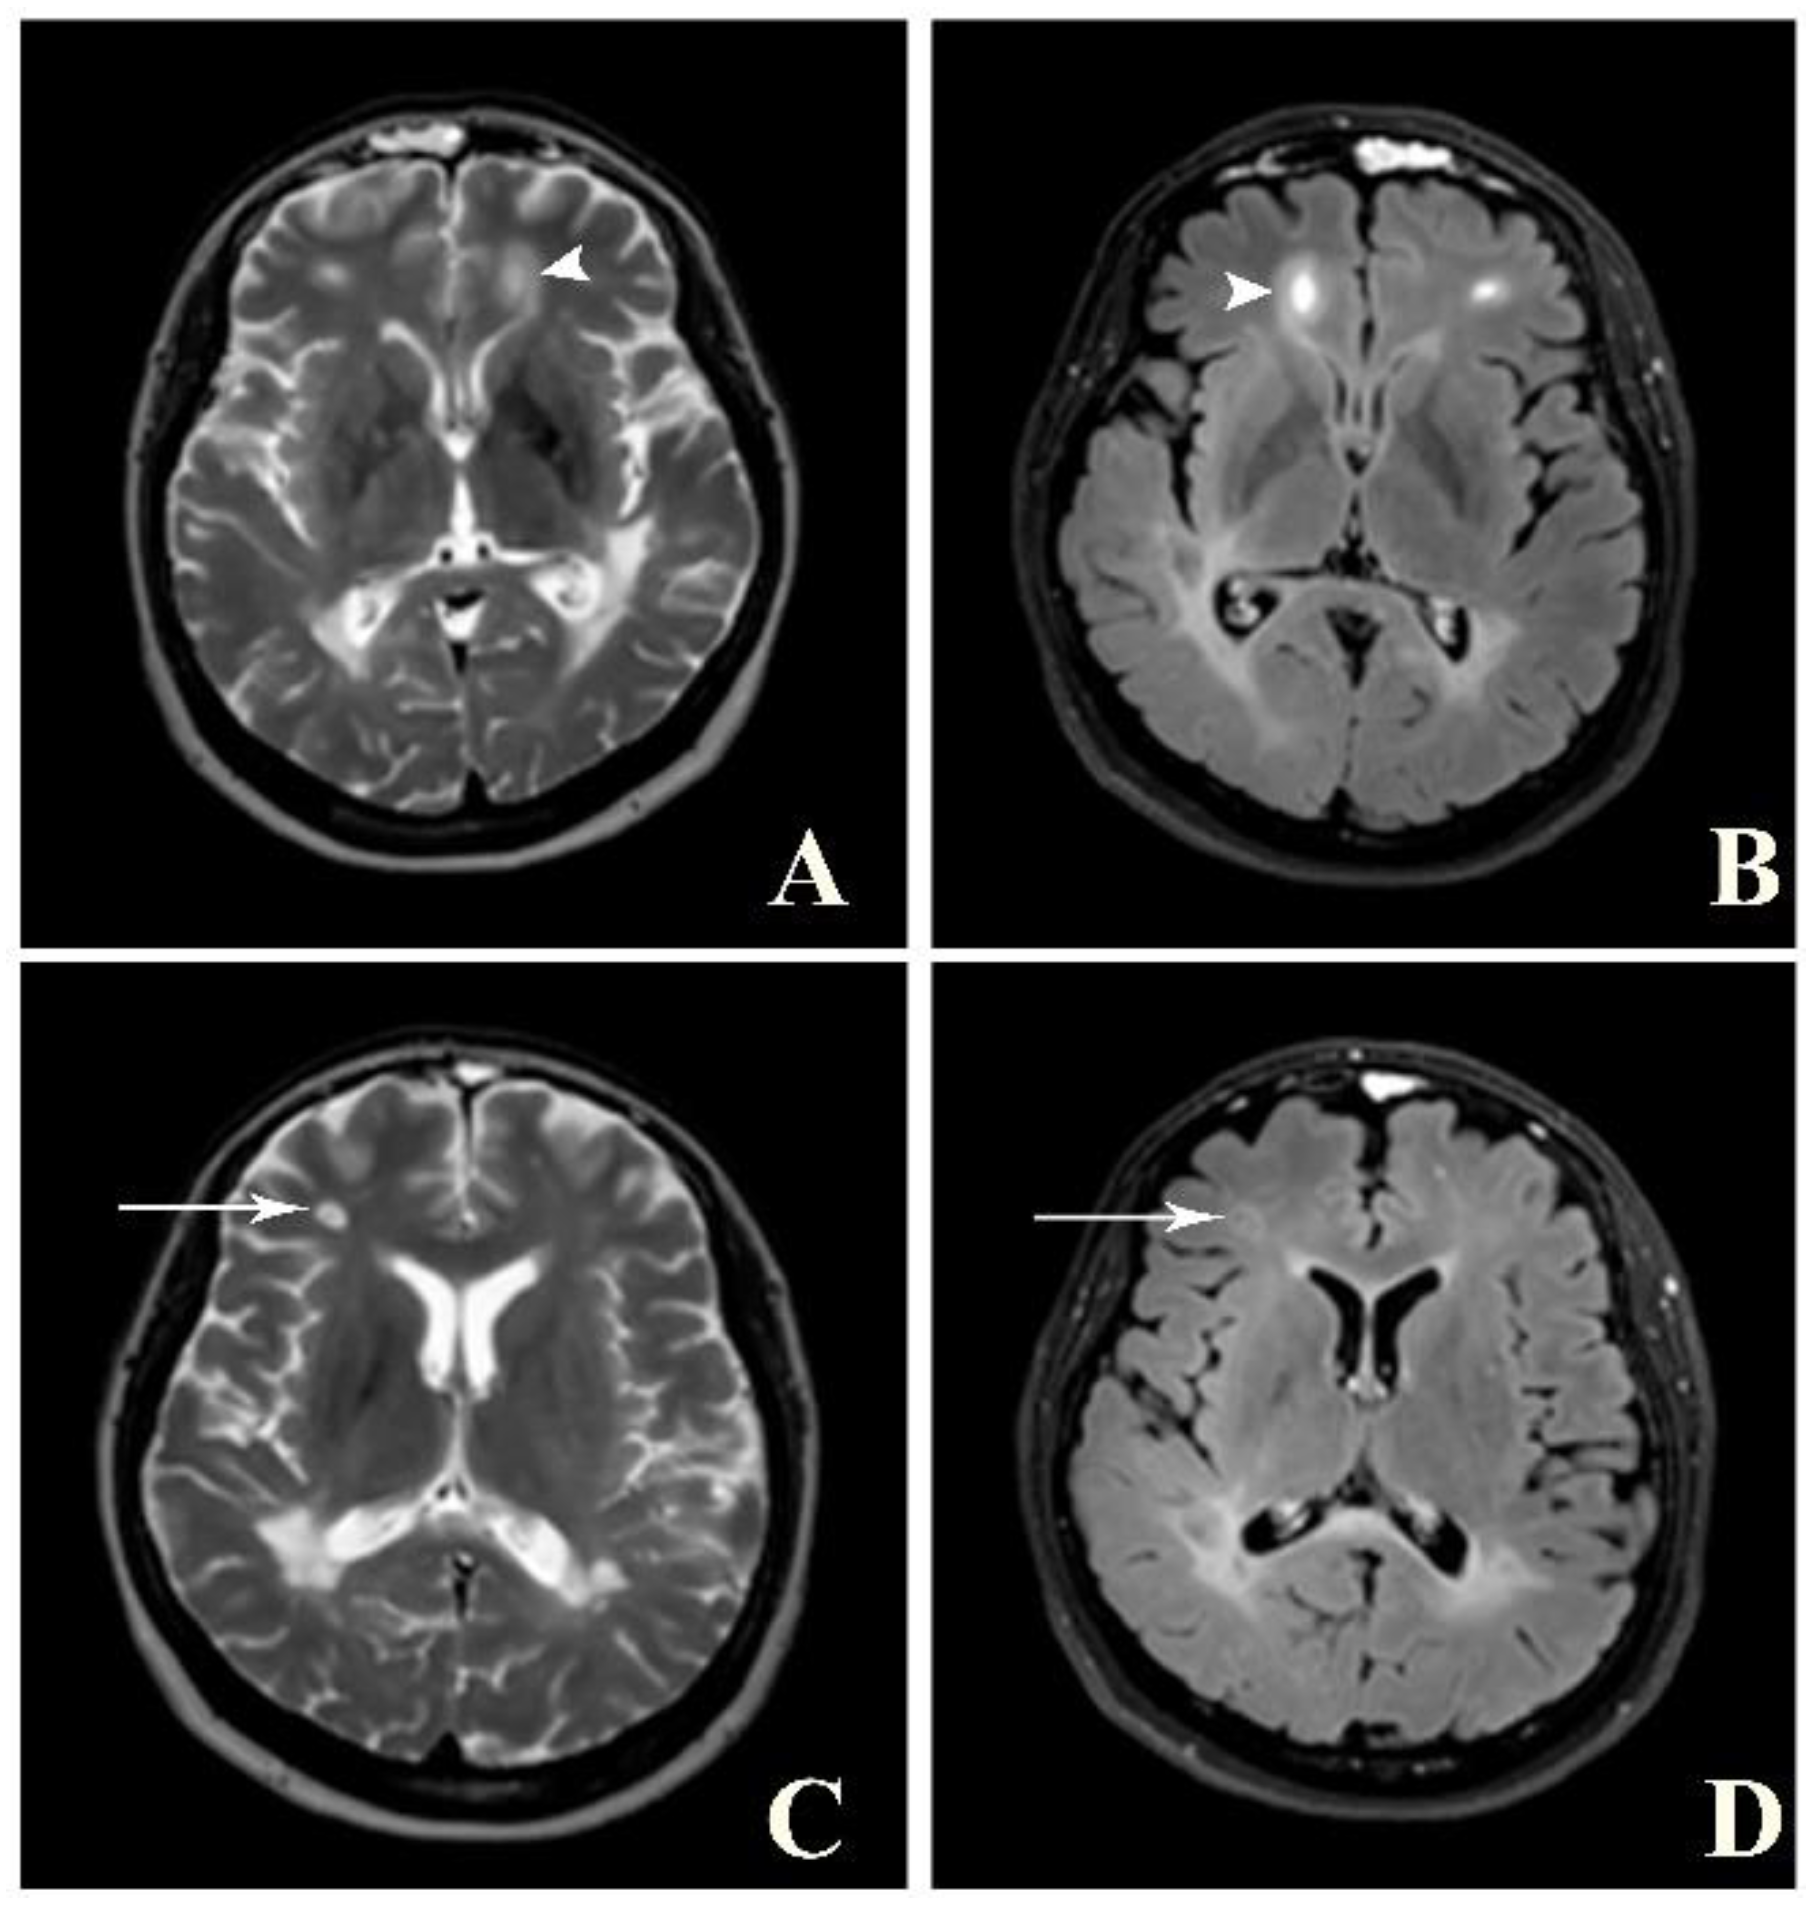

Figure 4. Balo’s concentric sclerosis. A and B: Axial T2W (A) and post-contrast FLAIR (B) images show a few lesions with alternating band of high and low signal intensity at bilateral frontal lobes (arrowhead). C and D: Axial T2W (C) and post-contrast FLAIR (D) images of the same patient show faint central and peripheral enhancement at the right frontal lobe lesion (arrow).

A brain MRI was available for all 32 patients, all of whom showed abnormalities. Most of the patients (19, 59.4%) were subjected to MRI soon after clinical presentation and during follow-up. The lesions were most commonly identified in the periventricular regions (78.1%), juxtacortical regions (75%) and deep white matter (62.5%). Cortical lesions were identified in only eight patients (25%). Other locations included in the McDonald criteria (2017) were the brainstem and cerebellum, which were found in 59.4 and 21.9% of all patients, respectively. The most common characteristic of the lesions was a round/oval discrete appearance (29 patients, 90.6%). A T1W-blackhole and classic Dawson’s finger (Figure 1) were equally identified in 20 patients (62.5%). A tumefactive form was found in two patients (Figure 2 and Figure 3). There were also two patients with target-like lesions, resembling Balo’s concentric sclerosis (Figure 4). The maximal diameter of the lesions was most commonly less than 13 mm (34.4%). A few patients showed lesions measuring more than 52 mm (9.4%), particularly those with confluent lesions. The total number of lesions in the T2W images was most commonly counted at less than 23 (50.0%), while there were up to four patients with extensive lesions, or more than 47 (12.5%) (Figure 5). Gadolinium-enhancing lesions were identified in nine patients (28.1%), who mostly only had one or two of these lesions (in five out of nine patients). Of these, the most common enhancing pattern was nodular enhancement (in four patients). The classic incomplete ring enhancement was identified in two patients, while complete ring enhancement was found in one patient. A visual assessment of the brain volume found brain atrophy in four patients (12.5%). Two patients with tumefactive MS showed brain swelling (Table 2).